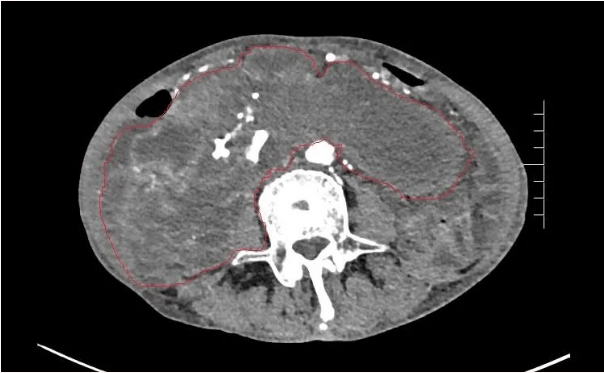

患者王大爺,男,72歲,發(fā)現(xiàn)腹腔腫物10余年,近兩年來(lái)患者雙下肢乏力、貧血,依靠間斷輸血維持著正常生活,出現(xiàn)頭昏,行動(dòng)困難,腹部疼痛及便血慕名來(lái)我院就診。入院后查體評(píng)估患者年齡大,體質(zhì)差,嚴(yán)重貧血,肺部感染及腸梗阻征象,腹部增強(qiáng)CT檢查提示腹膜后巨大腫瘤,長(zhǎng)徑超過(guò)30厘米,占據(jù)大部分腹腔,并可能存在雙原發(fā)腫瘤。

苗滿園腫瘤外科團(tuán)隊(duì)在麻醉科/手術(shù)室的緊密配合下為該患者進(jìn)行手術(shù),術(shù)中發(fā)現(xiàn)腫瘤巨大,幾乎占據(jù)了整個(gè)腹腔,從左側(cè)向右腹腔延伸,向上將肝、腎擠向膈下,向左將胃及小腸擠向左上腹,向下深達(dá)盆腔內(nèi),包繞下腔靜脈、腸系膜上動(dòng)脈等大血管及輸尿管,回盲部及回腸也受侵犯。手術(shù)難度巨大,風(fēng)險(xiǎn)極高。團(tuán)隊(duì)?wèi){借著高超的手術(shù)技能和精準(zhǔn)的手術(shù)預(yù)案沉著應(yīng)對(duì),迎難而上,應(yīng)用高頻電刀、超聲刀、切割縫合器等先進(jìn)設(shè)備,耗時(shí)近5小時(shí)為患者切除了巨大腹腔腫瘤,并聯(lián)合右半結(jié)腸切除,術(shù)中出血僅50ml。術(shù)后病理為腹膜后巨大平滑肌瘤+回腸腺癌。